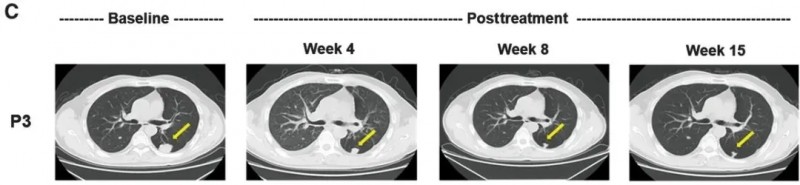

其中,患者P3与P13的治疗情况尤为值得关注,尤其是P3的疗效堪称亮眼——该患者为50岁男性,有2.2年多灶性肝癌病史,入组前GPC3 IHC染色强度评分为3+(强阳性);接受CAR-GPC3 T细胞治疗后,CT显示病灶从31.0×27.8mm缩小至12.2×9.5mm,经评估达到部分缓解(PR),无进展生存期(PFS)达111天,为晚期肝癌治疗提供了突破性范例。

▲图源“AACR”,版权归原作者所有,如无意中侵犯了知识产权,请联系我们删除